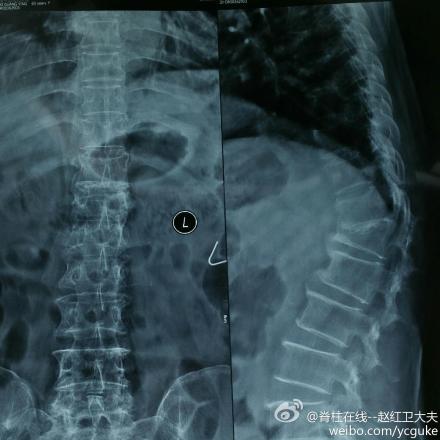

看起来有驼背脊椎有点侧弯从ct上看严重吗曾经有过一段时